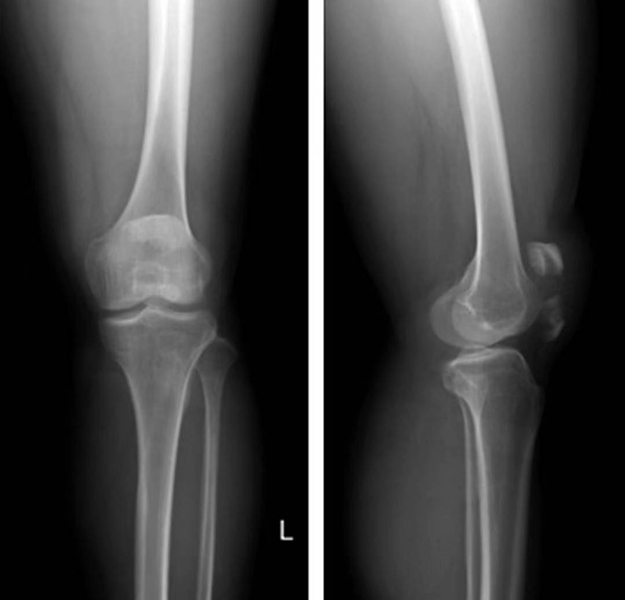

正常髌骨中心点应位于下肢轴线上或稍内侧(图1)。对于髌骨不稳定,膝关节正位像可见髌骨偏离正常的位置,向外侧移位(图2、图3)。

图2 膝关节正位X线成像显示了双侧髌骨偏离正常的解剖位置,明显向外侧移位